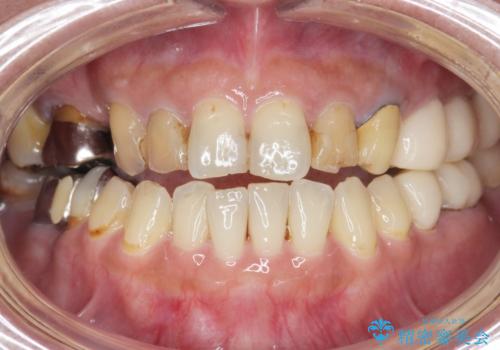

[ 破折し大きく吸収した歯槽骨 ] 他院では難しいと言われたインプラント治療

![[ 破折し大きく吸収した歯槽骨 ] 他院では難しいと言われたインプラント治療の症例 治療前](https://seimitsushinbi.jp/wp/wp-content/uploads/2024/10/073ce5e06775df372887a513b05b34d0-500x350.jpg?v=1729760111)